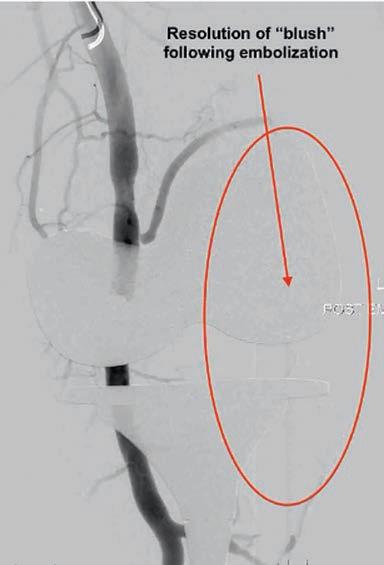

OUR PRINTER’S ACCREDITATIONS CONTENTS This magazine has been printed using solar electricity, and the paper is manufactured with elemental chlorine-free pulps. Both printer and paper manufacturer are certified to ISO 14001, the world’s highest environmental standard. Environment ISO 14001 MAJOR PARTNERS Clinicals 5 ATTR cardiac amyloid 2024 Dr Peter Purnell 34 What we can learn from top five CV trials of 2023 Dr Edmund Lee 36 Geniculate artery embolisation for knee osteoarthritis Drs Stefan Ponosh & Daniel Fick Guest Columns 10 Cardiac arrest, not your typical holiday activity Dr Mike Civil 29 Combatting health’s fraud risks Jayesh Kapitan & Roger Darvall-Stevens 30 Is dirty air linked to childhood dementia? E/Prof Odwyn Jones 39 Aortic stenosis – a 2024 update Prof David Playford 41 Strategies to reduce lifetime risk of CV events Dr Thato Mabote 44 Lipid clinics: Time to stop chewing the fat? A/Prof Chris Judkins 47 Effects of bariatric surgery on CV outcomes Dr Ravi Rao 48 Vascular disease and rapid weight loss in older adults By A/Prof Joshua Lewis & Dr Cassandra Smith 43 Abdominal aortic aneurysms Drs Nishath Altaf & Irina Baimatova